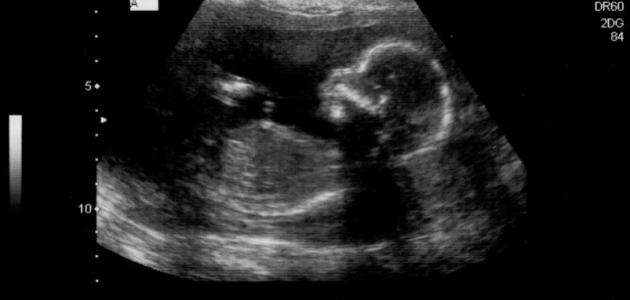

الجنين في الأسبوع السابع عشر

على الرغم من كل المتاعب التي تمر بها المرأة خلال فترة حملها سواء إن كانت صحية أو نفسية، إلّا أنّها تعتبر أجمل مراحل حياتها ابتداءً من اللحظة التي تكتشف فيها بأنّها حامل إلى حين ولادة طفلها ومشاهدته يتنفس بين يديها، والحمل الطبيعي هو الذي تكون مدته تسعة أشهر، ولكبل شهر منها تطورات مختلفة تطرأ على الأم والجنين، فكيف يكون الجنين في الأسبوع السابع عشر من الحمل وما هي التغيرات التي تطرأ عليه وعلى والدته في هذا الأسبوع؟[١]